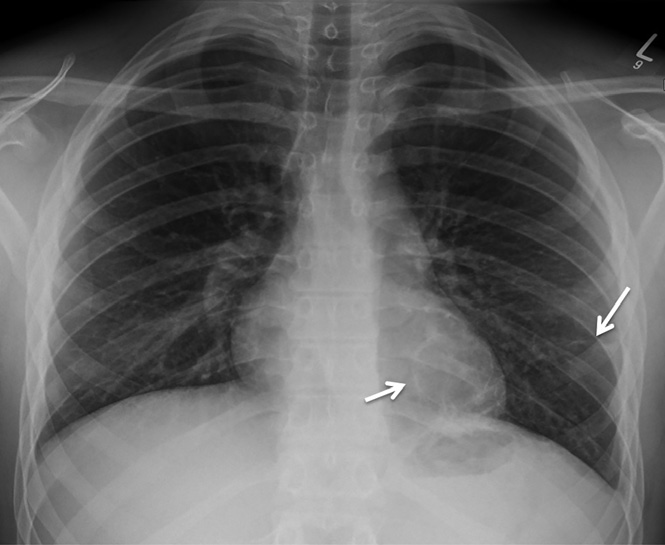

實驗室檢查顯示白細(xì)胞計數(shù)13.6×109/L↑(中性粒細(xì)胞79%;淋巴細(xì)胞12%),C反應(yīng)蛋白96 mg/L↑。胸部X線檢查顯示左肺下葉實變伴氣液平面,考慮與空洞性肺炎相關(guān)(圖1)。增強CT顯示左肺下葉病變,有空氣支氣管征和含氣液平面的空洞及囊狀氣腔。(圖2A–2 C)。人類免疫缺陷病毒抗體檢測、抗中性粒細(xì)胞胞漿抗體、尿肺炎球菌和軍團菌抗原檢測均為陰性,且多組血培養(yǎng)結(jié)果顯示無菌?;颊呦惹拔催M行IgG及亞類缺陷檢測。

圖1 胸部X線顯示左肺下葉實變伴氣液平面,未發(fā)現(xiàn)明確腫塊。該結(jié)果與空洞性肺炎相關(guān)。

圖2 軸向(A)、(B)和冠狀(C)CT圖像顯示左肺下葉病變伴空洞、氣液平面、相鄰囊性空腔和周圍實變。